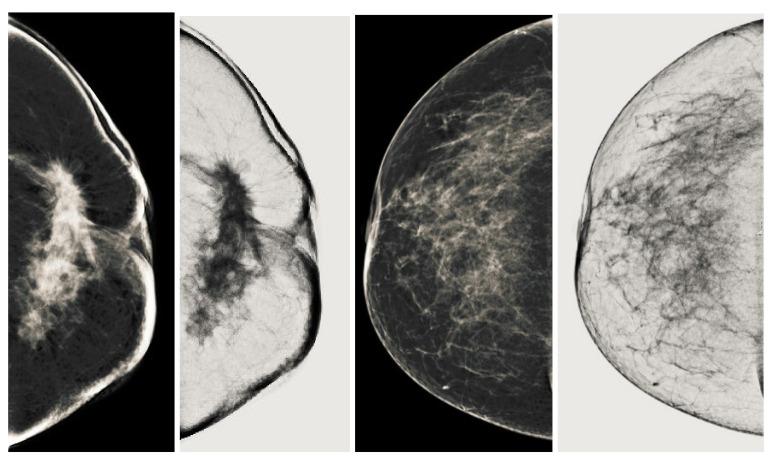

Breast cancer is widespread around the world and can be cured if diagnosed at an early stage. Digital mammograms are used as the most effective imaging modalities for the diagnosis of breast cancer. However, mammography images suffer from low contrast, background noise as well as contrast as non-coherency among the regions, and these factors makes breast cancer diagnosis challenging. These problems can be overcome by using a new image enhancement technique. The objective of this research work is to enhance mammography images to improve the overall process of segmentation and classification of breast cancer diagnosis. We proposed the image enhancement for mammogram images, as well as the ablation of the pectoral muscle. The image enhancement technique involves several steps. In the first step, we process the mammography images in three channels (red, green and blue), the second step is based on the uniformity of the background on morphological operations, and the third step is to obtain a well-contrasted image using principal component analysis (PCA). The fourth step is based on the removal of the pectoral muscle using a seed-based region growth technique, and the last step contains the coherence of the different regions of the image using a second order Gaussian Laplacian (LoG) and an oriented diffusion filter to obtain a much-improved contrast image. The proposed image enhancement technique is tested with our data collected from different hospitals in Qassim health cluster Qassim province Saudi Arabia, and it contains the five Breast Imaging and Reporting System (BI-RADS) categories and this database contained 11,194 images (the images contain carnio-caudal (CC) view and mediolateral oblique(MLO) view of mammography images), and we used approximately 700 images to validate our database. We have achieved improved performance in terms of peak signal-to-noise ratio, contrast, and effective measurement of enhancement (EME) as well as our proposed image enhancement technique outperforms existing image enhancement methods. This performance of our proposed method demonstrates the ability to improve the diagnostic performance of the computerized breast cancer detection method.